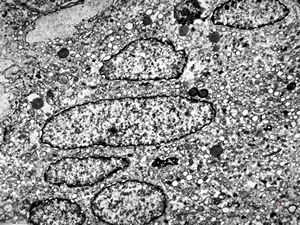

M, 70y. | mycosis fungoides - Sézary cell